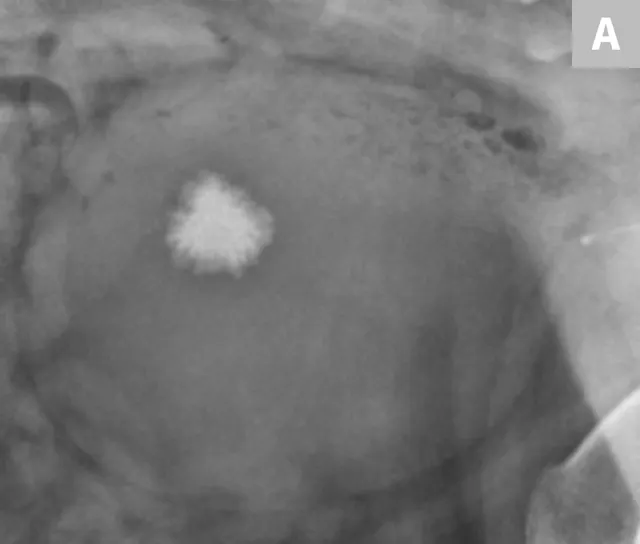

FIGURE 8A

Lateral radiograph of the urinary bladder in a dog with a confirmed calcium oxalate calculus. This calculus has a very irregular margin often seen with calcium oxalate calculus formation.